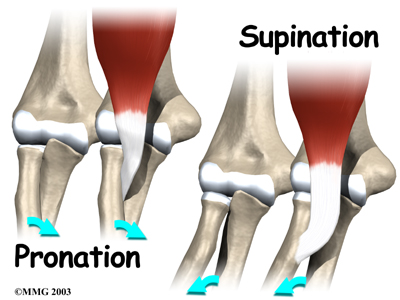

can bend the elbow upward. The biceps can also help flex the shoulder, raising the arm up. And the biceps can rotate, or twist, the forearm in a way that points the palm of the hand up. This movement is called . Supination positions the hand as if you were carrying a tray.

Not having surgery often results in significant loss of strength. Flexion of the elbow is somewhat affected, but supination (which is the motion of twisting the forearm, such as when you use a screwdriver) can be very affected. A distal biceps rupture that is not repaired reduces supination strength by about 50 percent.